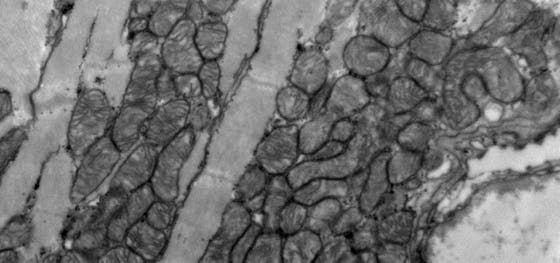

Researchers from the group of Jeroen Bakkers discovered that mutations in the gene Tnnt2a cause a severe form of cardiomyopathy in zebrafish. The fish undergo structural cardiac changes, increased stress and stiffening of the wall of the heart. Additionally, they are subjected to changes in heart rhythm, contraction and calcium sensitivity. These traits are similar to those observed in human cardiomyopathies, which makes the model ideal for research into drugs for this type of disease. The results were published in the special issue on ‘Zebrafish Heart Development, Regeneration and Disease Modelling’ in the Journal of Cardiovascular Development and Disease on April 20th.